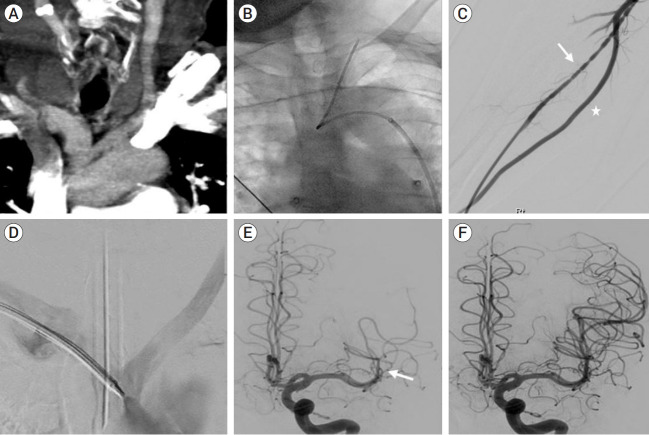

84 years old gentle man with past medical history of hypertension and diabetes presented with sudden onset right sided weakness and aphasia for two hours. Initial neurological assessment revealed National Institute of Health Stroke Scale (NIHSS) 17. Computed tomography (CT) scan demonstrated minimal early ischemic changes along left insular cortex with occlusion of left middle cerebral artery (MCA). Based on clinical and imaging findings, decision was made to perform mechanical thrombectomy procedure. Initially, right common femoral artery approach was utilized. However, due to unfavorable type-III bovine arch, left internal carotid artery could not be engaged via this approach. Subsequently, access was switched to right radial artery. Angiogram revealed small caliber radial artery, with larger caliber ulnar artery. Attempt was made to advance the guide catheter through the radial artery, however significant vasospasm was encountered. Subsequently, ulnar artery was accessed and successful thrombolysis in cerebral infarction (TICI) III left MCA reperfusion was achieved with a single pass of mechanical thrombectomy via this approach. Post procedure neurological examination demonstrated significant clinical improvement. Doppler ultrasound 48 hours after the procedure demonstrated patent flow in radial and ulnar arteries with no evidence of dissection.